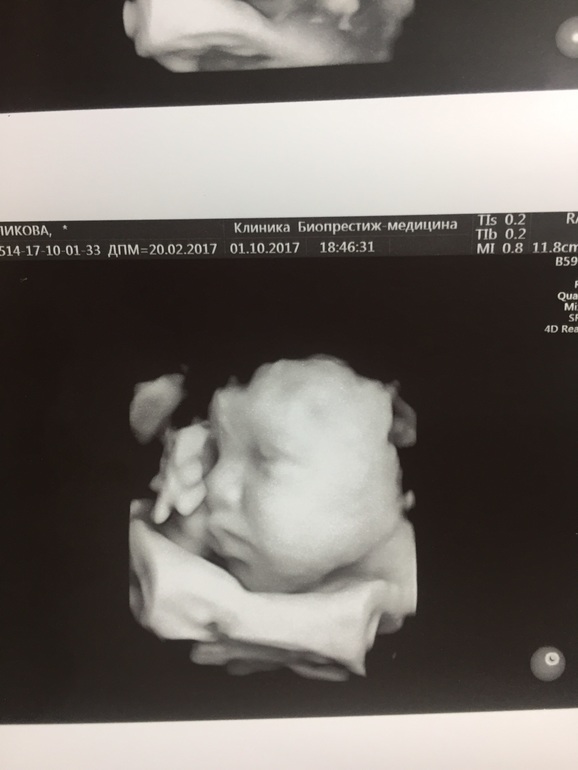

В общем с такими болями к 32 неделям я кардинально поменяла своё мнение и на приёме у врача сказала: не хочу сама рожать))) В 32 недели едем на УЗИ к Пятых и она нам: вот это мужичок!! Вес 2700🙈 мы, конечно, опережали всё время, но не на 4 недели. Вот наш щекастик))